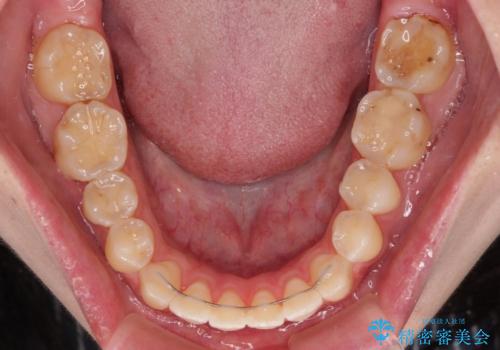

開咬を治す インビザラインによる矯正治療

- 上下前歯の開咬を気にして来院された患者様です。

開咬はインビザラインを用いると有意に改善ができるため、インビザラインによる矯正治療を行うこととしました。

途中1年8ヶ月ほど来院されず、久しぶりの来院後は治療が面倒とのことで、前歯の叢生や隙間に不十分な点が残った状態での終了となりました。